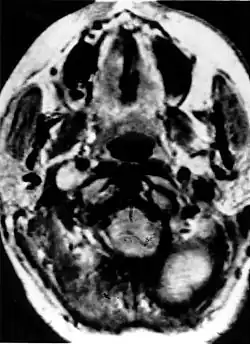

Narząd słuchu

Na tle zespołu von Hippla-Lindaua może rozwinąć się rzadki guz worka endolimfatycznego (ELST, od ang. endolymphatic sac tumor). Nowotwory tego typu rozwijają się u około 10% pacjentów[3]. Charakteryzuje się on miejscową złośliwością: rozrasta się, niszcząc piramidę kości skroniowej i struktury ucha wewnętrznego, czego następstwem jest różnego stopnia upośledzenie słuchu, do całkowitej głuchoty włącznie. Guz może też naciekać nerwy czaszkowe – twarzowy i przedsionkowo-ślimakowy. ELST rośnie w kierunku móżdżku i kąta móżdżkowo-mostowego, w sposób przypominający inne nowotwory tej lokalizacji. Stwierdzenie guza tylnego dołu czaszki o takim typie wzrostu u pacjenta z rozpoznaną chorobą von Hippla-Lindaua albo z dodatnim wywiadem rodzinnym jest w zasadzie równoznaczne z rozpoznaniem ELST – doniesienia o guzach splotu naczyniówkowego[12], gruczolakach[13] i gruczolakorakach u pacjentów z HLS prawdopodobnie w rzeczywistości dotyczyły guzów worka endolimfatycznego[14]. Histologicznie ELST nie jest naczyniakiem zarodkowym, przypominając raczej torbielakogruczolaka brodawkowego najądrza[14].